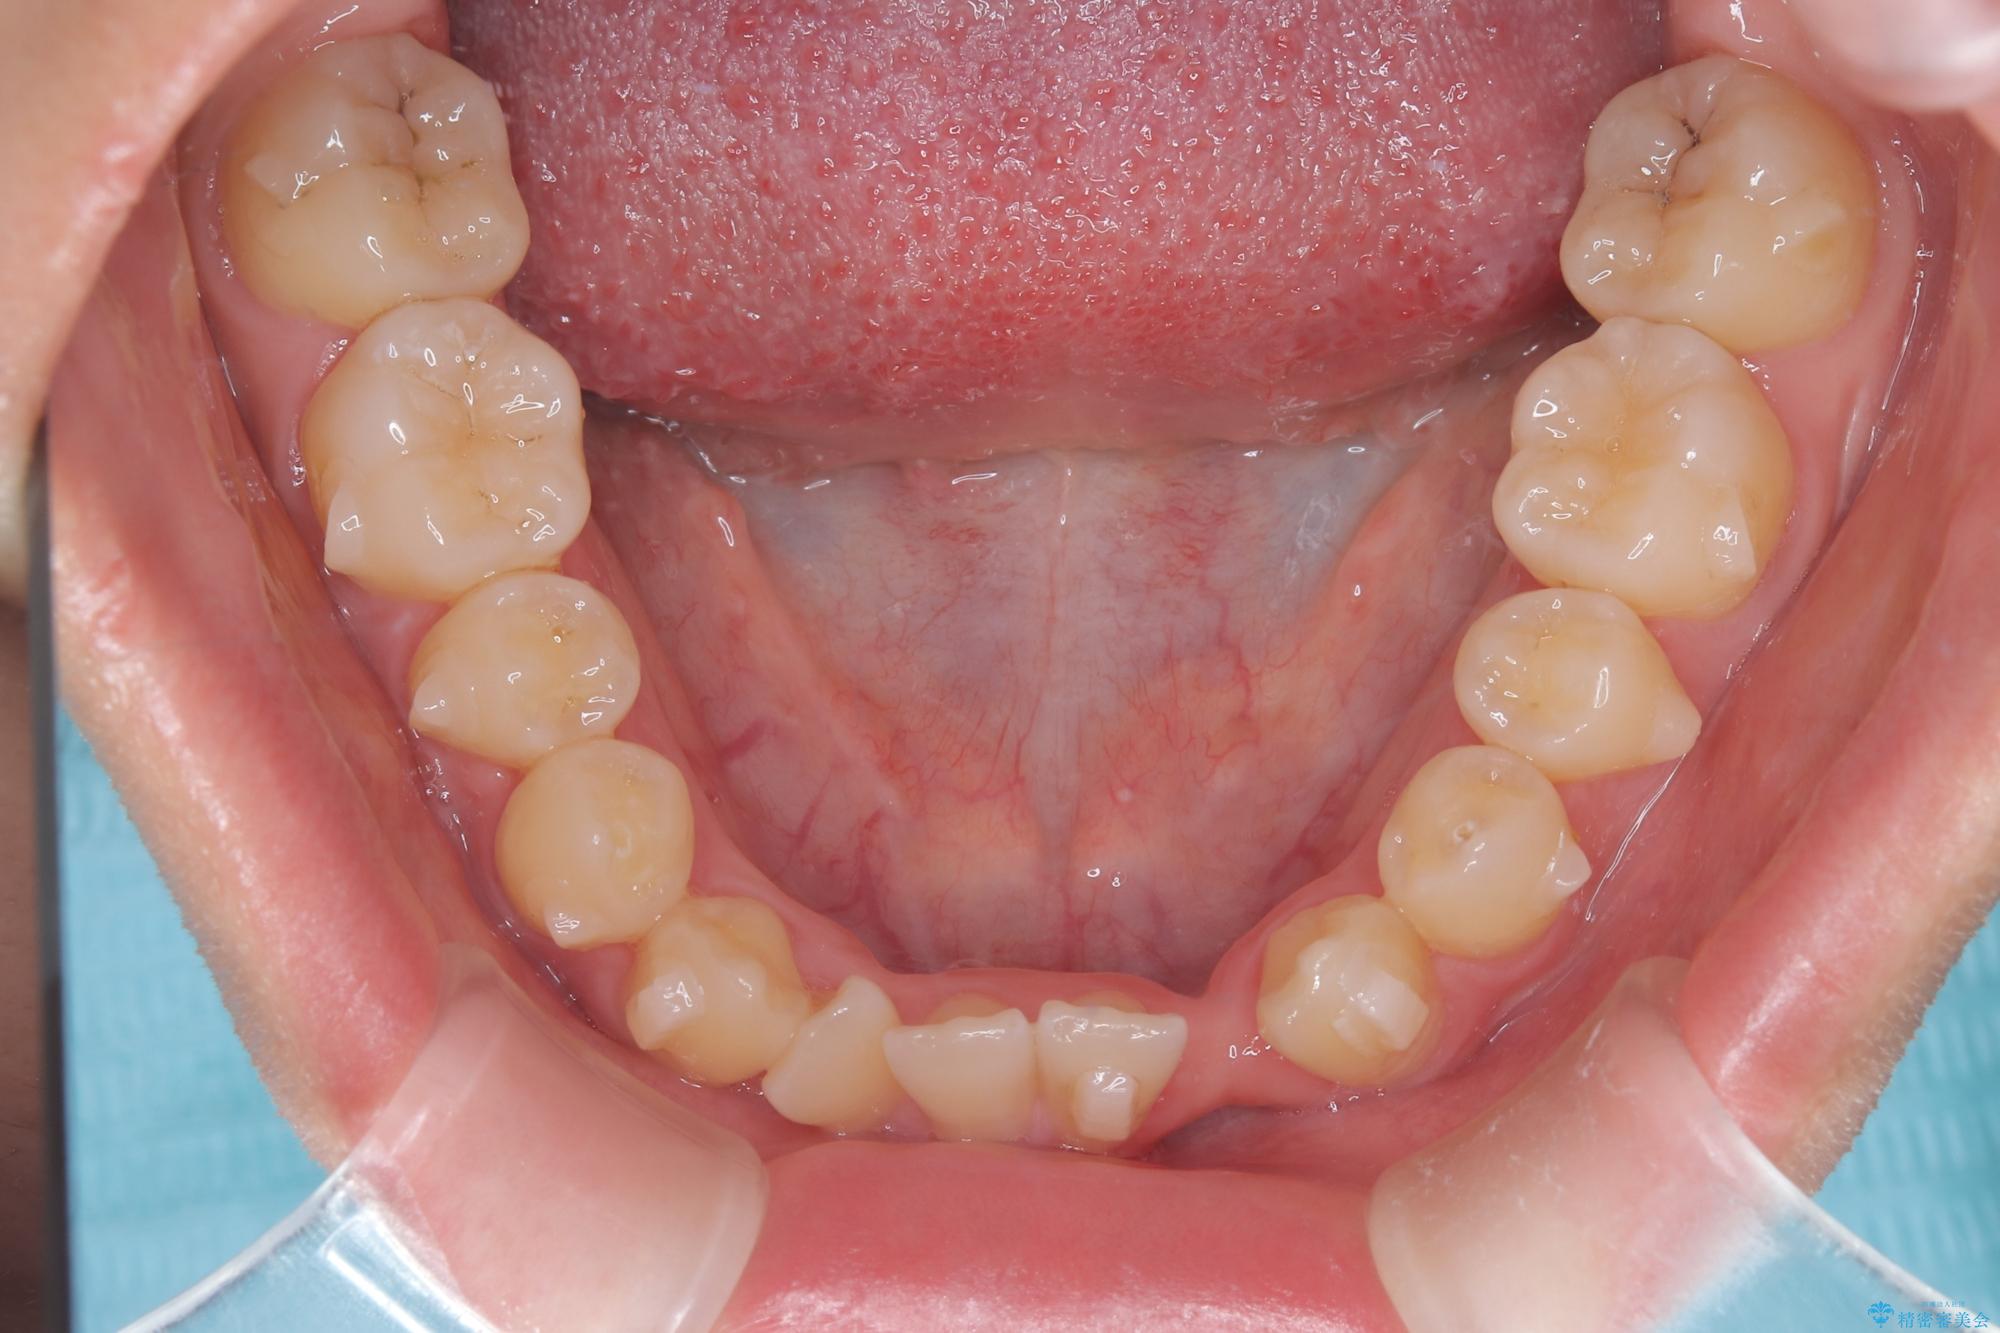

診査の結果、すでに下顎前歯の抜歯が行われていましたが、マウスピースの適合が著しく悪くなっており、歯が計画通りに動いていない状態でした。また、歯を支える骨の厚みや歯肉の薄さを考慮すると、このままマウスピースによる傾斜移動を続けるのは歯肉退縮(歯茎が下がること)のリスクが非常に高いと判断。

安全かつ確実に抜歯スペースを閉じ、咬み合わせを完成させるため、マウスピースから**ワイヤー矯正(マルチブラケット装置)**へ切り替えるリカバリープランを提案しました。